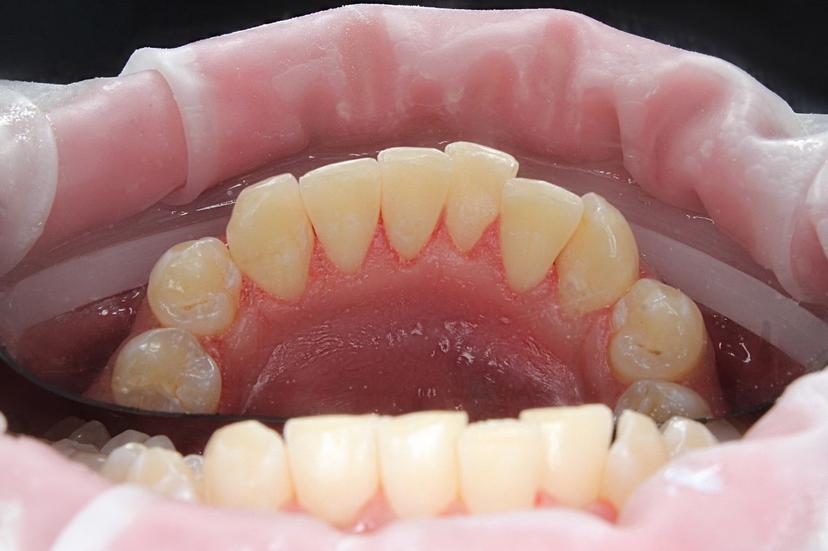

Пациент обратился с жалобами на зубные отложения: пигментированный зубной налет, мягкий зубной налет, наддесневой и поддесневой минерализованный зубной камень.

Удаление наддесневыз зубных отложений: пигментированный зубной надет, минерализованный зубной камень.

Пациент обратился с жалобами на зубные отложения: пигментированный зубной налет, мягкий зубной налет. Наддесневой и поддесневой минерализованный зубной камень.

Пациент обратился с жалобами на наросты на зубах: мягкий зубной налет, наддесневой и поддесневой минерализованный зубной камень.